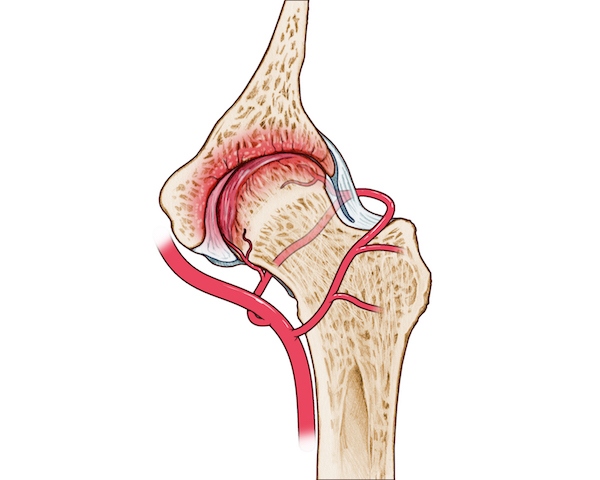

نکروز سر استخوان ران یا استئونکروز، وضعیتی است که در آن خون‌رسانی به قسمت بالایی استخوان ران، یعنی سر استخوان فمور، مختل می‌شود. این اختلال باعث مرگ بافت استخوانی می‌گردد و در نهایت می‌تواند منجر به فروپاشی استخوان و آسیب به مفصل ران شود. مفصل ران یک مفصل گوی و کاسه‌ای است که سر استخوان ران (گوی) در حفره استابولوم (کاسه) قرار می‌گیرد و با غضروف پوشیده شده تا حرکت نرم و روان را فراهم کند. این بیماری نباید با مشکلات عملکردی مفصل ران مانند سندرم اسنپینگ هیپ که بیشتر با صدا دادن یا گیر کردن مفصل همراه است، اشتباه گرفته شود.

علت اصلی سیاه شدن سر استخوان ران، کاهش یا قطع جریان خون به استخوان است. این مشکل می‌تواند ناشی از عوامل مختلفی باشد که در ادامه به آن‌ها اشاره می‌کنیم:

شکستگی گردن استخوان ران یا دررفتگی مفصل ران می‌تواند به رگ‌های خونی آسیب برساند و خون‌رسانی را مختل کند. این آسیب‌ها اغلب در اثر تصادفات یا زمین خوردن رخ می‌دهند.